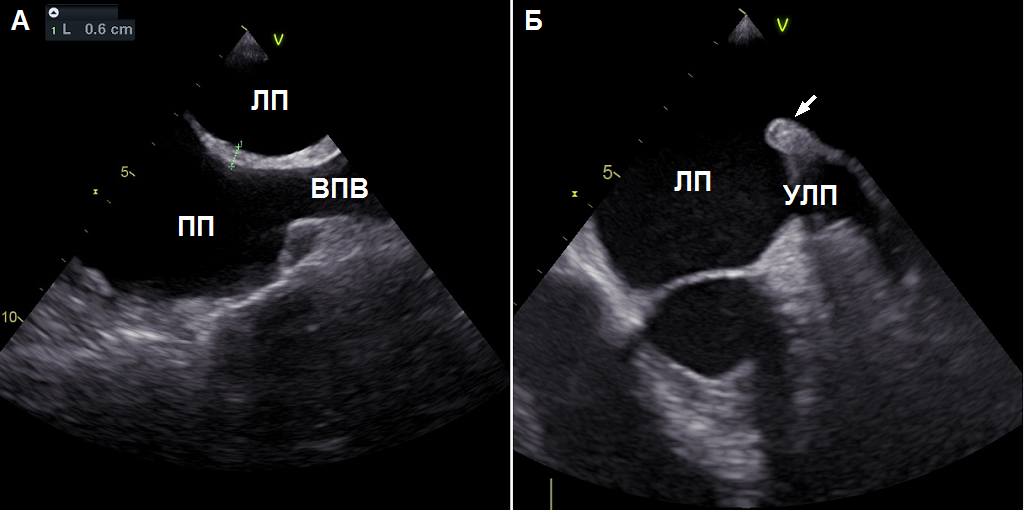

Высокую точность измерения большинства предсердных структур обеспечивает чреспищеводная ЭхоКГ, которая широко используется при подготовке больных ФП к кардиоверсии и катетерной аблации. Методику измерения толщины МПП (рис. 2А) еще в 2005 году предложили A. Lopez-Candales et al. [17], однако чреспищеводная ЭхоКГ не получила широкого распространения в исследованиях, посвященных изучению взаимосвязи между количеством периатриального жира и ФП. Между тем, чреспищеводная ЭхоКГ позволяет визуализировать такие содержащие эпикардиальный жир структуры, как кумадинов гребень (рис. 2Б) и атриовентрикулярная борозда [28]. Заметим, что содержащийся в этих структурах эпикардиальный жир находится в непосредственной близости от ушка левого предсердия, служащего главным местом образования тромбов у больных ФП. Возможно, именно ЧПЭхоКГ сыграет ведущую роль в изучении взаимосвязи между эпикардиальным ожирением и риском развития тромбоэмболических осложнений при ФП.

Рисунок 2. Чреспищеводное эхокардиографическое исследование: А — измерение толщины межпредсердной перегородки в бикавальной позиции, Б — левый боковой гребень (помечен стрелкой) в двухкамерной позиции со срезанной верхушкой сердца из среднего отдела пищевода.

Примечание. ЛП — левое предсердие, ПП — правое предсердие, ВПВ — верхняя полая вена, УЛП — ушко левого предсердия.